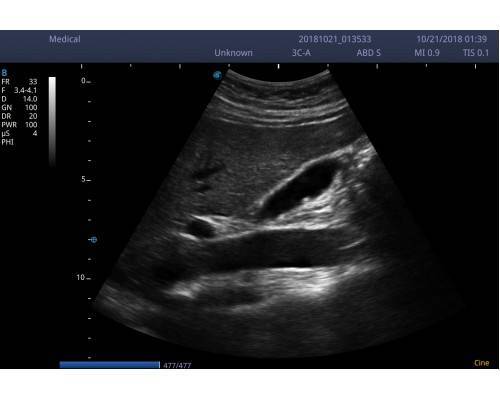

και μοντέρνας εμφάνισης του. Εξυπηρετεί τις ανάγκες όλων σχεδόν των ειδικοτήτων

• Εικόνα 2 διαστάσεων 2D (B mode),2B(δίπλες εικόνες), 4B(τετραπλές εικόνες), M mode, PW (pulse wave Doppler,CFM (color),PDI(power)DirPDI (κατεύθυνση ροής )CW .

• THI(αρμόνικες συχνότητες )

• Pulse inversion harmonic imaging(δημιουργεί αντίθεση μεταξύ των ιστών έχοντας κατά συνέπεια πολύ καλύτερη ποιότητα εικόνας.

• Spatial compound imaging(σάρωση από διαφορετικές οπτικές γωνίες σε πραγματικό χρόνο πολύ καλύτερη απεικόνιση)

• M-scan (speckle reduction technology, αλγόριθμος που αυξάνει την ποιότητα της εικόνας κατά πολύ.)

3C-A (ABD-OB-GYN) 1.O-7.0MHZ 50mm